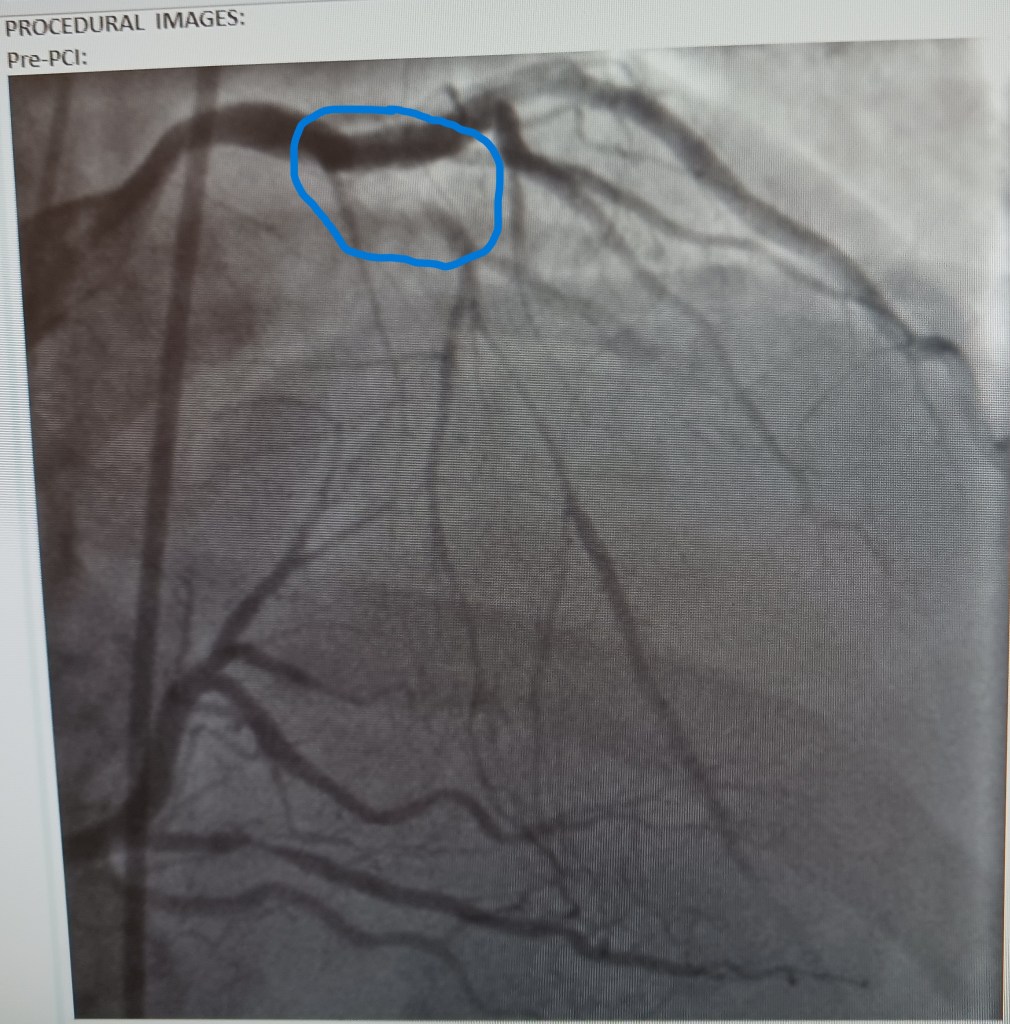

But that was 2023. I would shortly learn that I had developed a 100% blockage in my “widow maker” artery. At the time I was running the SF half that year, I had no clue. But I should have known. What I didn’t know was that the blockage was likely well above 80% and was getting ready to close. But there was no chest pain, which is the warning sign that something serious is about to happen. Then again, my cardiologist didn’t know either because was not feeling pain.

My cardiologist and I agreed that it was time for drastic measures to deal with the arrhythmia: an ablation procedure. But then the events of September of 2023 happened, and we had to prevent a serious or fatal myocardial infarction from possibly ending my life. Luckily, we got that fixed just in time.